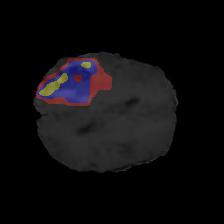

Brain tumor segmentation. Segmenting tumors in brain is challenging due to the high variance in appearance and shape of the tumors [28]. We use a subset of the 2017 Brain Tumour Image Segmentation (BraTS) dataset [29, 26]. It contains multi-parametric 3D MRI scans. The segmentation masks include (possibly overlapping) three classes of tumor. The 3D scans are split into 2D image slices, and only images that contain at least one tumor class are retained. Figure 7 shows three MSGNet generated samples as well as the corresponding masks. Since MSGNet adheres to the underlying relationships between various classes, we see that the generated images and the masks for different tumor classes are in line with the images and masks from the training set. In general, MSGNet rarely generated erroneous samples; we found roughly one sample per 3000 generations that could be rejected. Similar to the malaria experiment, we observed an improvement of 3.1% () in -score on the validation set.

A subset of the BrATS dataset was used. We used the images accompanied by segmentation layouts from the FLAIR and T1Gd modes. The segmentation layouts showed the sub-regions for three different classes: GD-enhancing tumor, the peritumoral edema, and the necrotic and non-enhancing tumor core. The brain and the background were treated as an additional class. We refer to [32] for further details. For the two modes, the background has been modelled using two different classes. We only considered half of the 155 slices, i.e., we took only the even-numbered slices and out of those we discarded the slices that did not include one of the previously mentioned tumor-classes in order to create a more balanced dataset. This resulted in 20,000 images that were further augmented with 6,000 MSGNet generated images. Example generations of the masks as well as the images are shown in Figure 12.